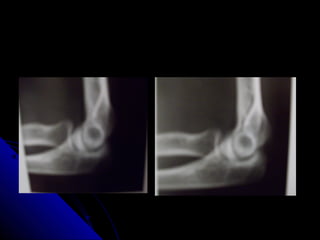

PROYECCION LATERALPROYECCION LATERAL

 El codo va flexionado a 90º.El codo va flexionado a 90º.

 Se puede ver el olècranon de perfil.Se puede ver el olècranon de perfil.

 Hay que tener en cuenta, que enHay que tener en cuenta, que en

extensiòn parcial o completa, el olècranonextensiòn parcial o completa, el olècranon

eleva la almohadilla grasa posterior yeleva la almohadilla grasa posterior y

simula patología articular. (De ahì lasimula patología articular. (De ahì la

importancia de que la flexiòn del codo seaimportancia de que la flexiòn del codo sea

a 90º.a 90º.

 Una almohadilla grasa anterior visible esUna almohadilla grasa anterior visible es

un hallazgo normal, pero elun hallazgo normal, pero el

desplazamiento anterior de èsta sugieredesplazamiento anterior de èsta sugiere

existencia de una fractura.existencia de una fractura.

 Una almohadilla grasa posterior visibleUna almohadilla grasa posterior visible

siempre es un hallazgo patològico. Essiempre es un hallazgo patològico. Es

posible que exista una fractura.posible que exista una fractura.

 En la proyecciòn lateral:En la proyecciòn lateral:

 El còndilo y la troclea se superponenEl còndilo y la troclea se superponen

 En una rfìa lateral estricta se puede trazar unaEn una rfìa lateral estricta se puede trazar una

lìnea a lo largo de la cortical anterior dellìnea a lo largo de la cortical anterior del

hùmero. En la mayorìa de los pacientes, aprox,hùmero. En la mayorìa de los pacientes, aprox,

un tercio del còndilo es anterior a esta lìnea.un tercio del còndilo es anterior a esta lìnea.

 Si menos de un tercio del còndilo es anterior aSi menos de un tercio del còndilo es anterior a

esta lìnea , hay que sospechar una fracturaesta lìnea , hay que sospechar una fractura

supracondìlea con desplazamiento posterior delsupracondìlea con desplazamiento posterior del

fragmento distal.(esta norma no siempre esfragmento distal.(esta norma no siempre es

fiable en niños muy pequeños particularmentefiable en niños muy pequeños particularmente

cuando hay una osificaciòn parcial del còndilo.cuando hay una osificaciòn parcial del còndilo.

 Una lìnea trazada a lo largo del centro deUna lìnea trazada a lo largo del centro de

la diàfisis del radio proximal deberìa pasarla diàfisis del radio proximal deberìa pasar

a travès del còndilo.a travès del còndilo.

 Si esta lìnea no pasa a travès del còndilo,Si esta lìnea no pasa a travès del còndilo,

es probable la luxaciòn de la cabeza deles probable la luxaciòn de la cabeza del

radio.radio.

 Esta norma es siempre vàlida si se aplicaEsta norma es siempre vàlida si se aplica

a las rfìas que son estrictamente laterales.a las rfìas que son estrictamente laterales.